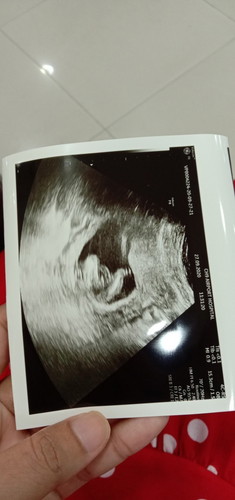

แม่ๆว่า ญ/ช ค่ะ ซาวมาหมอบอกว่าเปอร์เซ็นเป็นผู้ชายแต่ยังไม่แน่ใจ แม่ลุ้นมากค่ะ แม่ก็ดูไม่ค่อยเป็น รบกวนแม่ๆดูช่วยหน่อยนะค่ะ🥰🥰 แม่บ้านนี้อยากได้หญิงพ่ออยากได้ชายค่ะ